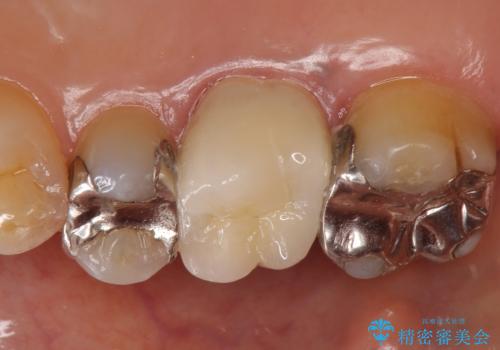

根管治療も希望されたため、再根管治療終了後、オールセラミッククラウンによる補綴を行いました。

今回用いたオールセラミッククラウンはジルコニアフレームという白い素材の上にセラミックを盛っているため、審美性が非常に高いのが特徴です。

また、ジルコニアは人工ダイヤモンドの材料にも使われているほど高い強度を持っており、そのためオールセラミッククラウンは審美性だけでなく、奥歯やブリッジの補綴も可能とするクラウンです。